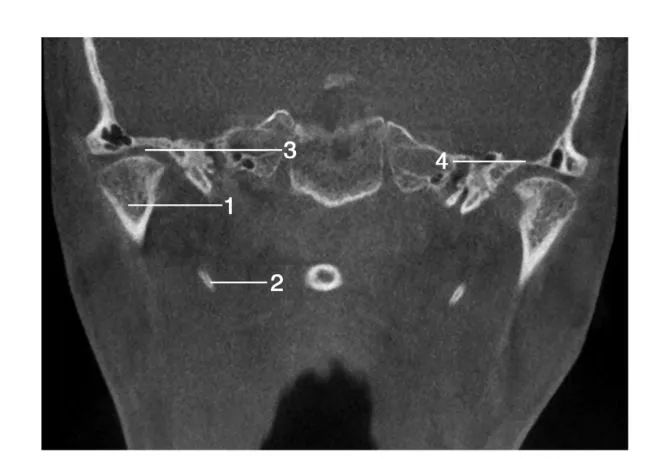

经下颌双侧髁突处层面冠状位图像

1.髁突; 2.茎突; 3.关节间隙 ; 4.关节凹顶部